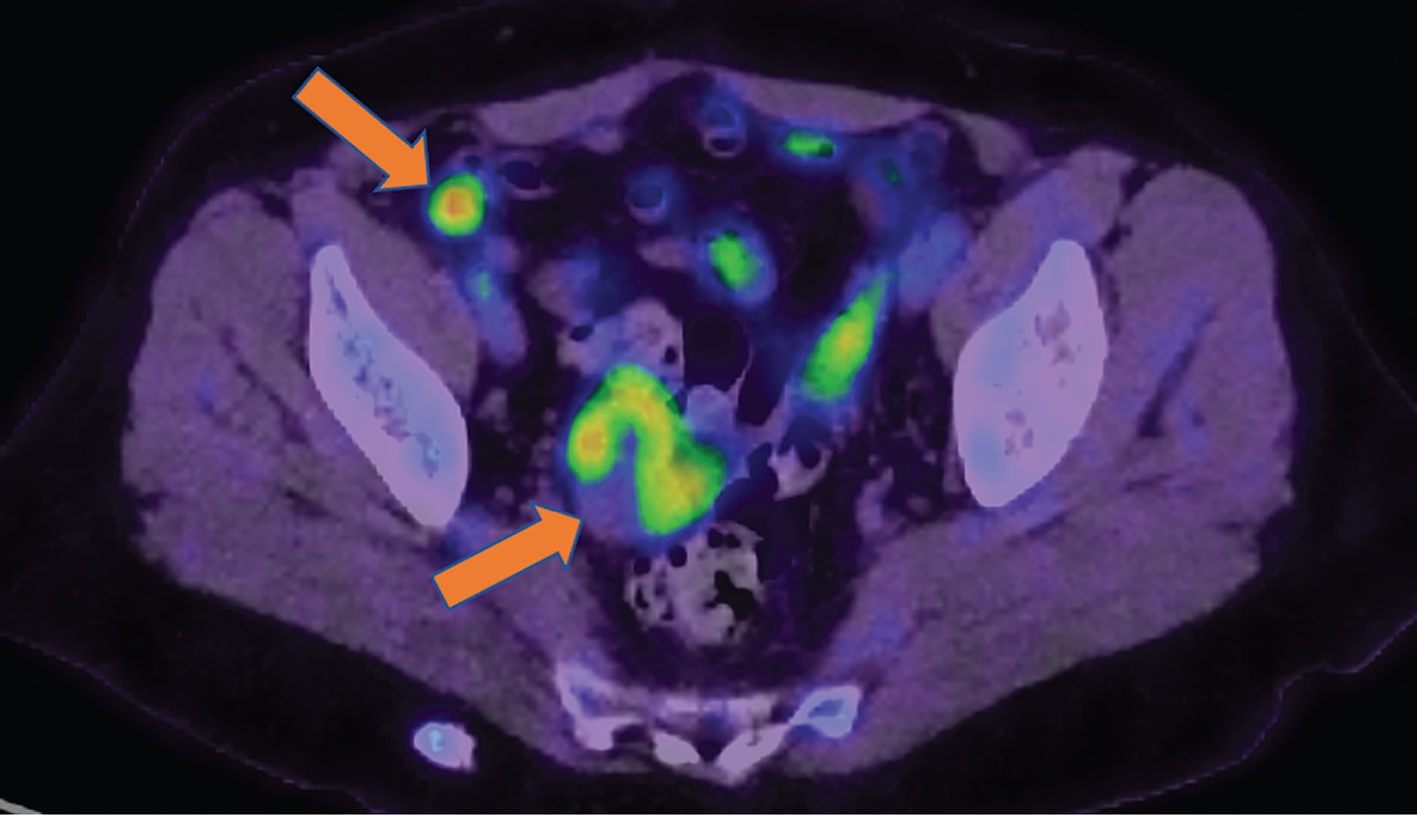

Fig 3

Figure 3. Restaging. 18F-FDG PET/CT images obtained from a 69-yr-old patient with Stage IIIC ovarian carcinoma, post debulking surgery and completion of 3rd line chemotherapy, referred for restaging (in the absence of baseline imaging). Arrows indicate the metabolically active primary ovarian tumor in the right adnexa and a right-sided metastatic iliac lymph node.

Suspected recurrence

PET/CT imaging with 18F-FDG has a very high sensitivity rate of 85–100% for detection of recurrence in ovarian cancer (Figure 3), compared to CECT 18F-FDG is more sensitive and more specific; with a sensitivity 91% vs. 84% for CECT and specificity of 91% vs. 65% (35). In addition, 18F-FDG PET/CT gives information about the extent and location of disease which helps in deciding the best treatment approach (23). In comparison to CA-125, CECT, and MRI, FDG PET/CT showed a better sensitivity in detecting ovarian cancer recurrence and distant spread (28); in addition, 18F-FDG PET/CT can identify recurrence earlier before morphological changes occur, because recurrence is characterized by hypermetabolism (36). 18F-FDG PET/CT upstages patients which leads to change in management of a significant proportion of patients by detecting extra-abdominal metastases or sites of diseases anatomically inaccessible for cytoreductive surgery. In a study by Fulham et al., surgery was avoided in 54% of patients who were initially candidates for surgery before the PET/CT; chemotherapy was added to the treatment of 16% and avoided in 13% (37). 18F-FDG PET/CT impacts management by allowing for the selection of the most appropriate treatment and avoids the morbidity and mortality as well as cost associated with the invasive procedure.